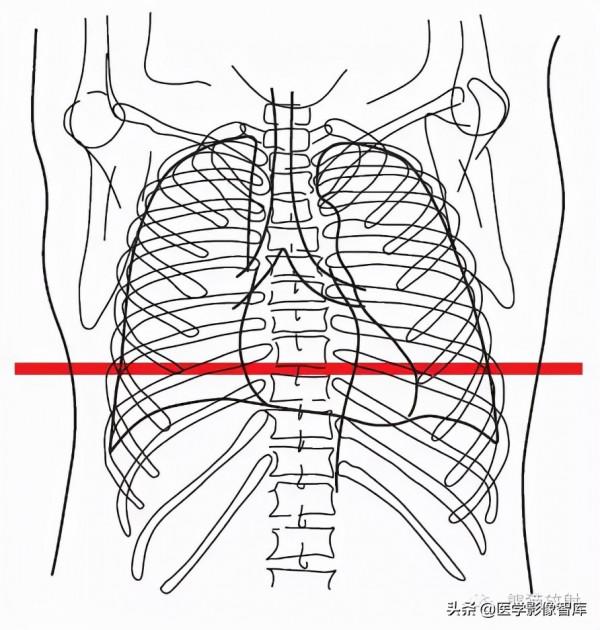

第十三層:心底水平

6. Diaphragm 膈肌

10. Base of heart 心底